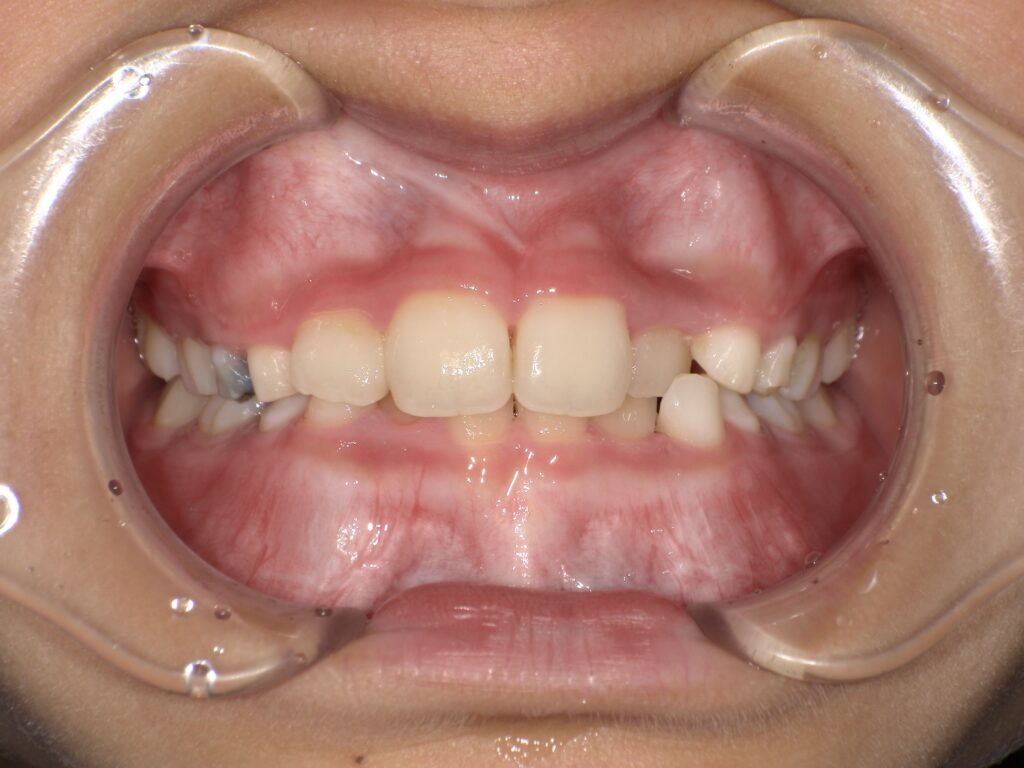

【過蓋咬合】

噛んだ時に上の前歯が下の前歯を覆い隠してしまっているような噛み合わせのことを「過蓋咬合」と呼びます。

このタイプは上顎が下顎を覆っているために、顎の可動域が制限されます。

また、下顎前歯が上顎の歯茎に刺さって傷つけてしまうこともあります。

過蓋咬合は顎が後方へ押し込められることにより関節に無理な力がかかる